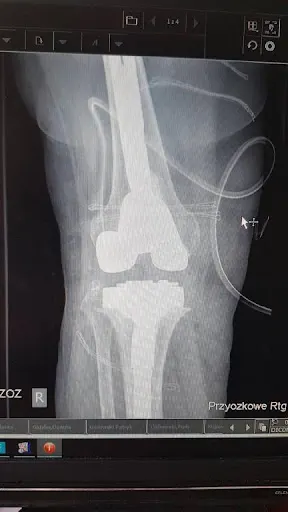

Dr Paweł Cieśla, doktor nauk medycznych i specjalista ortopedii, prowadzi praktykę lekarską w Gdyni przy ul. Armii Krajowej 44/26. W swojej działalności skupia się na diagnostyce i leczeniu schorzeń układu ruchu, w tym skomplikowanych operacjach stawów i kręgosłupa. Gabinet cieszy się oceną 4.3/5 w Google na podstawie 14 opinii pacjentów, co odzwierciedla mieszane doświadczenia osób korzystających z jego usług. Wielu pacjentów chwali doktora Cieślę za skuteczność w operacjach ortopedycznych. Jedna z pacjentek, leczona od ponad 10 lat, podkreśla udane endoprotezy obu kolan, które pozwoliły jej wrócić do normalnego chodzenia, oraz planowany kolejny zabieg stopy. Inni wspominają o profesjonalnej opiece po operacjach stawu biodrowego czy kolan, gdzie po zabiegu ból ustąpił, a ruchomość wróciła bez potrzeby silnych leków przeciwbólowych. Pacjenci doceniają też rutynowe podejście do trudnych przypadków, jak złamania kręgosłupa i miednicy, choć w niektórych relacjach operacje realizowano w szpitalach partnerskich. Nie brakuje jednak głosów krytycznych. Część opinii wskazuje na szybkie konsultacje prywatne, problemy z rachunkami czy powikłania po wstrzyknięciach, np. kwasu hialuronowego, prowadzące do dalszych zabiegów. Mimo to dr Cieśla utrzymuje pozycję lokalnego specjalisty, do którego wracają lojalni pacjenci z Trójmiasta. (198 słów)